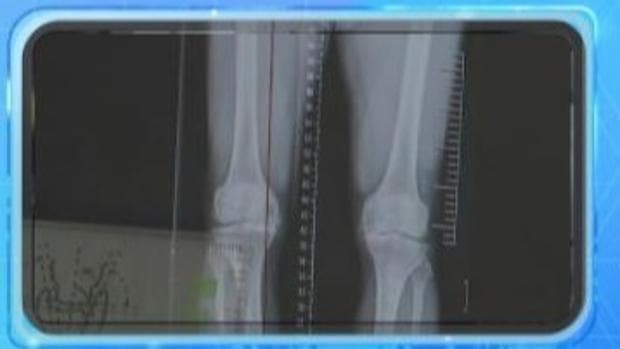

最近,世界关节炎日的到来引发了人们对关节健康的关注。然而,关节问题并非仅限于老年群体,长期保持伏案姿势、热衷运动或存在体重超标的人群同样需要警惕。

根据北京大学第三医院骨科关节外科主任田华的解释,天气变冷会导致下肢血管收缩,局部血液循环减少,从而加剧关节不适。同时,湿度和气压的变化也可能刺激关节内部机制,导致不适感。